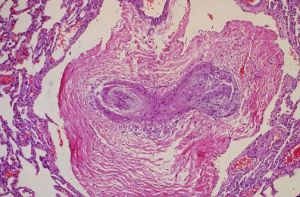

肺動脈高壓引起的叢狀損害1.左心疾病相關性肺動脈高壓

約占全部肺動脈高壓的78.8%.高血壓、糖尿病、冠心病等疾病的後期經常會並發心功能不全,在中、重度患者中會引起肺循環血流動力學改變和肺血管重構,進一步導致肺動脈高壓。